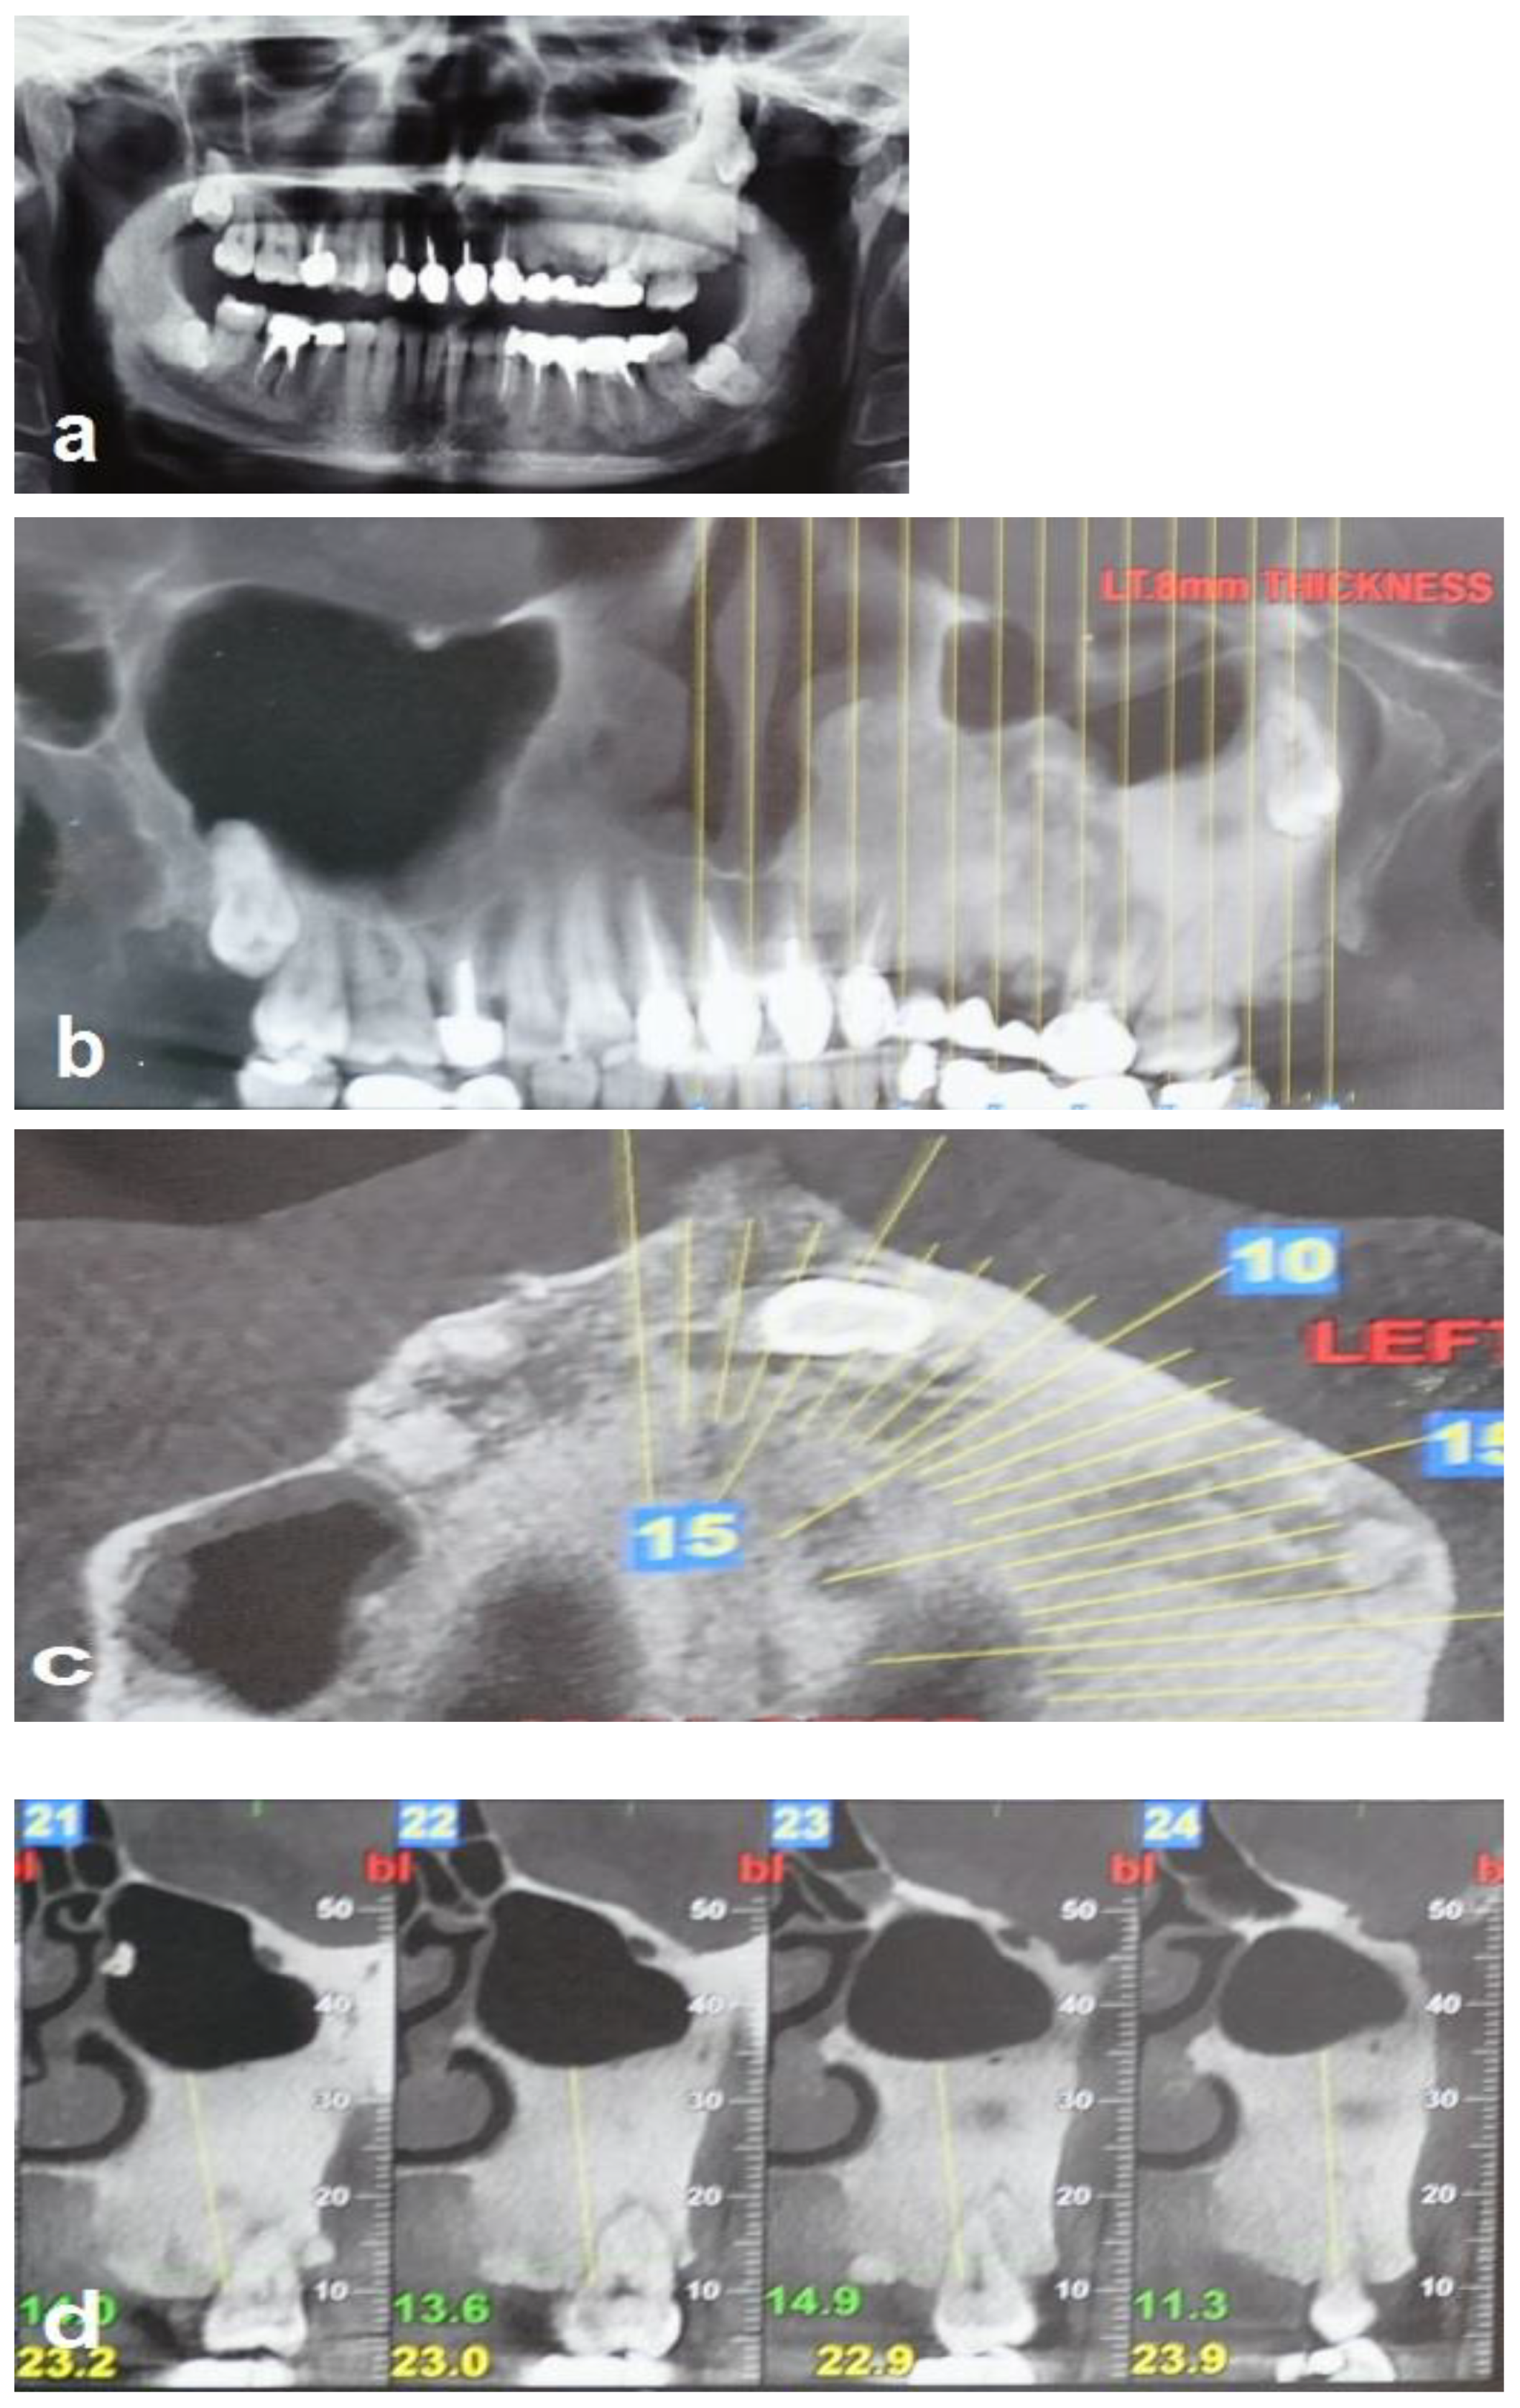

A 35-year-old woman was referred to the maxillofacial department for tooth extractions and dental implant placement in her left posterior maxillary segment. The referral was due to a suspected unidentified bone lesion in this region observed by her dental practitioner. She was an otherwise healthy patient. On examination, mild facial asymmetry was observed in her left malar area with mild expansion, without any neurological or cosmetic complaints (Figure 1). Intraoral examination revealed mild expansion of the vestibular left posterior maxillary ridge. An old fixed bridge extending from the left incisor to the first molar restored a missing canine, and first and second premolars. The first molar registered pain on percussion. Radiographic evaluation revealed a hyperdense “ground glass appearance” and sclerotic bone lesion affecting the left maxilla, left malar bone, and inferior and lateral orbital rims of the same side (Figure 2a–d).

Figure 2. Radiographic views demonstrate that the FD lesion involves the left zygomaticomaxillary complex. (a,b) Panoramic radiograph and coronal CBCT show a hyperdense lesion in the left hemi-maxilla with displacement of the left maxillary sinus and the wisdom tooth, respectively. (c) Axial CBCT shows the hyperdense lesion involving the left maxilla, and (d) sagittal (cross-sectional) CBCT shows bone sclerosis and the displacement of the left maxillary sinus.